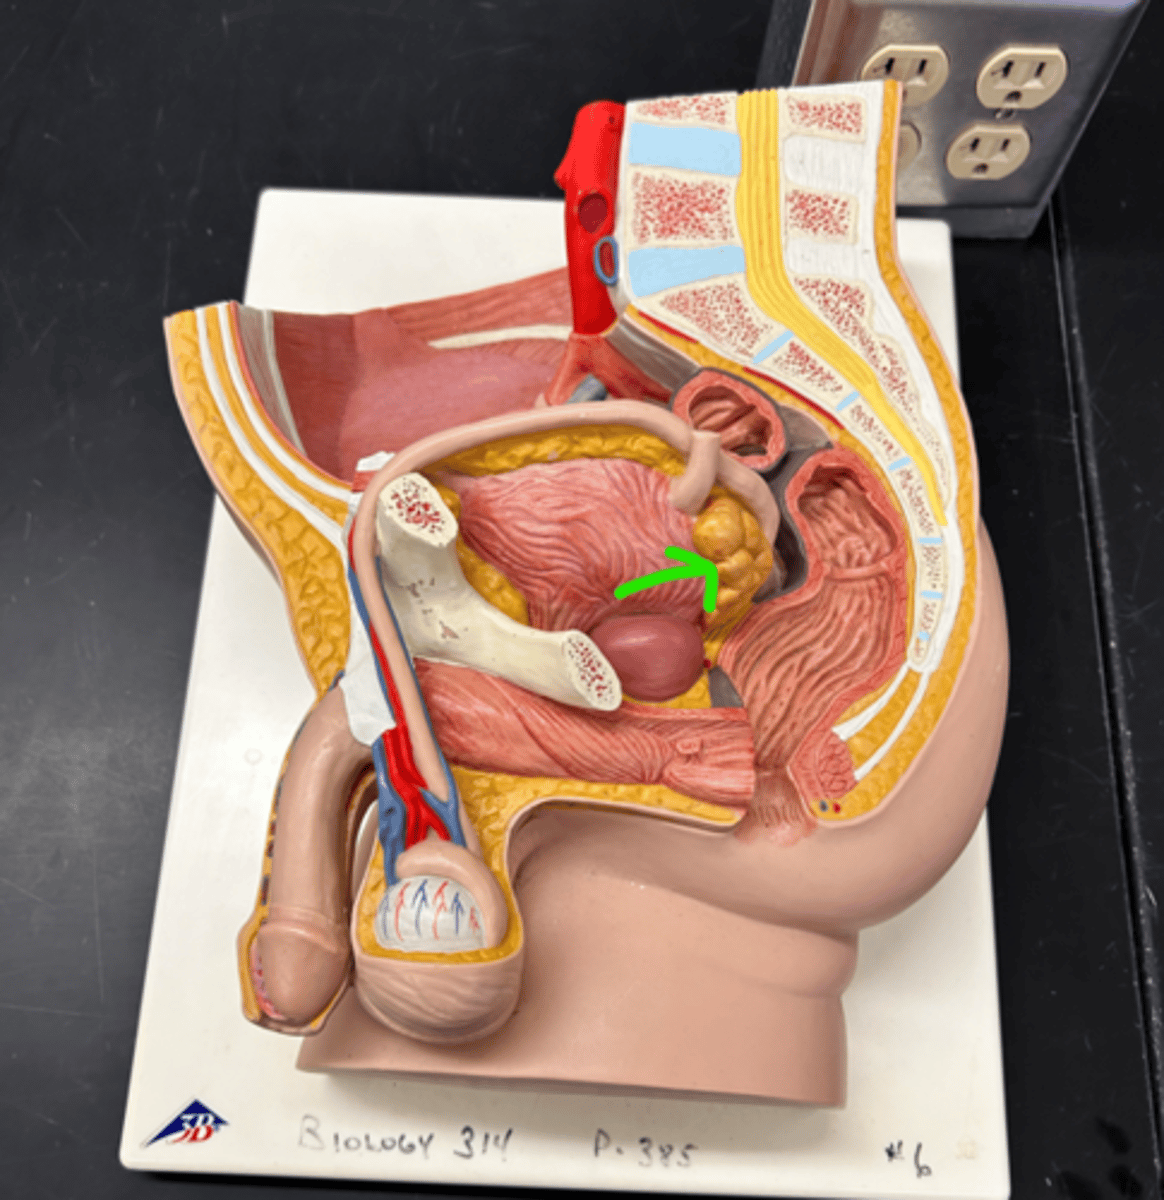

Chapter 30 Anat Phys: Male Reproductive System

Prostate gland